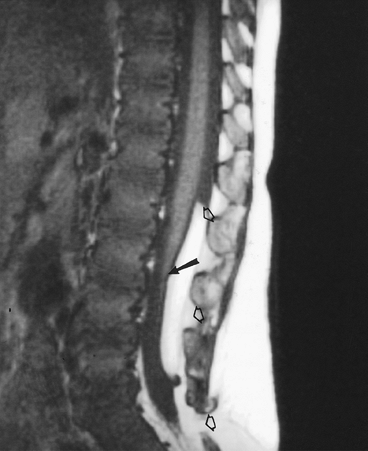

FIGURE 3-67 Neurofibroma. Oblique radiographs of the cervical spine show normal foramina in (A) and marked expansion in (B) (arrow). Coronal MR image (C) demonstrates a large neurofibroma extending through the foramen and displacing the cord.

FIGURE 3-68 Ependymoma. (A) Proton density-weighted sagittal image shows a well-defined intradural mass separate from the conus (curved arrow). (B)

Large mass in a different patient arising from the filum terminale on enhanced T1-weighted image. There is a second smaller metastatic lesion (arrow) distally. |